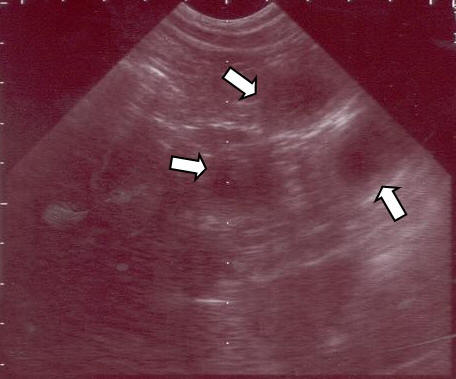

Die Trächtigkeit Die Geburt & 1. Woche 3. Woche